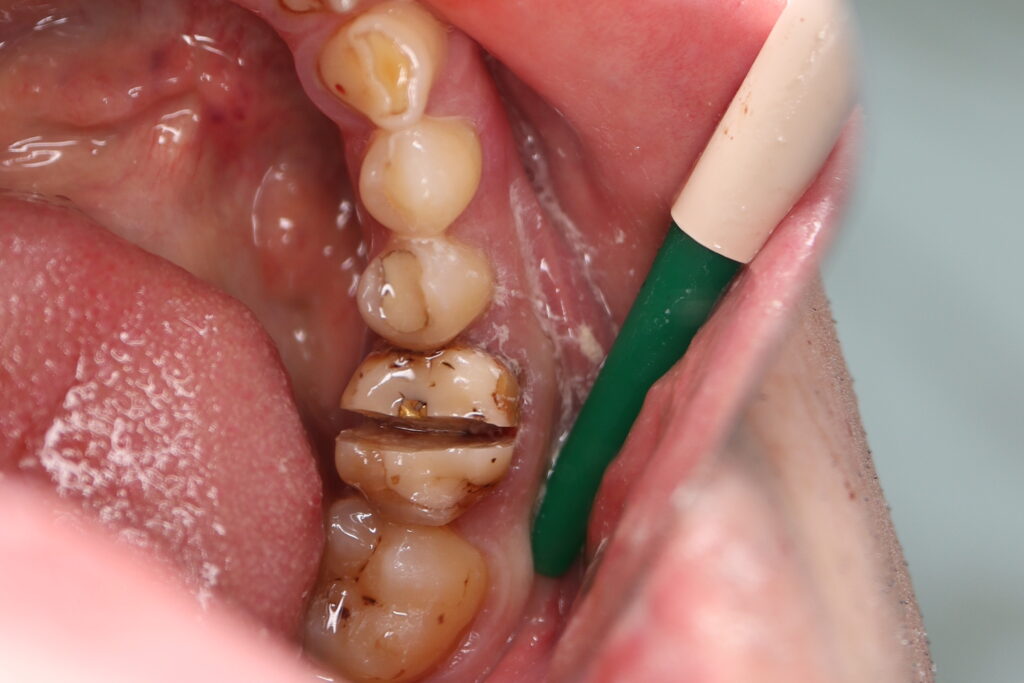

хирургический этап

Это фото может содержать тяжелый для восприятия контент

Были установлены 4 имплантата Straumann BLT. На верхней челюсти в области зуба 2.1 в одно посещение был установлен имплантат и изготовлена временная коронка.

Произведено препарирование зубов на верхней и нижней челюстях с контролем глубины (0.7-0.8 мм) под керамические виниры и коронки. Сняты оттиски на своих зубах и имплантатах.